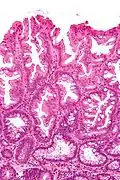

Faible grossissement x24: Adénome festonné sessile.

La partie profonde des glandes est souvent élargie, a tendance à se diviser en deux ou trois branches et à s’horizontaliser, c'est-à-dire à se disposer parallèlement à la musculaire muqueuse et non pas perpendiculairement à elle, comme dans les polypes hyperplasiques conventionnels et les adénomes festonnés traditionnels.